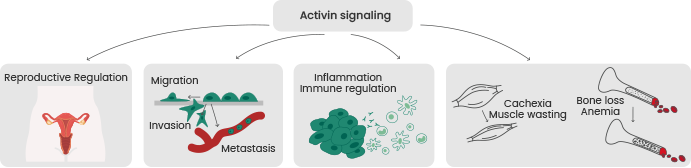

The TGFβ superfamily's activins and inhibins are best recognized for controlling reproductive physiology. Diseases such as neurological problems and reproductive disorders like polycystic ovary syndrome and prostate and ovarian cancer are caused by imbalances in activins and inhibins.

For instance, Activin A, which is predominantly encoded by inhibin β A (INHBA), has garnered significant attention due to its involvement in inflammation and fibrosis pathways. The diverse functions of activins and inhibins underscore their potential as valuable targets for the diagnosis, prevention, and treatment of various diseases across a broad spectrum.

Image Credit: Sino Biological Inc.